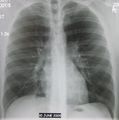

| A chest X-ray showing a very prominent wedge shaped pneumonia in the right lung. | |

Normal AP CXR

Normal lateral CXR